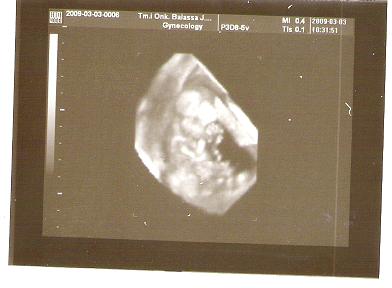

Tegnap voltam 12 hetes UH-n... olyan jó volt! Hallottam babónk szívhangját... és láttam is... ez egy CSODA!

Megpróbálok majd képet berakni....

A méretei: CRL 6,6 cm, NT: 0,17 cm

Minden normális... nagyon ficánkolt a kicsikém... a doki alig bírta lemérni...